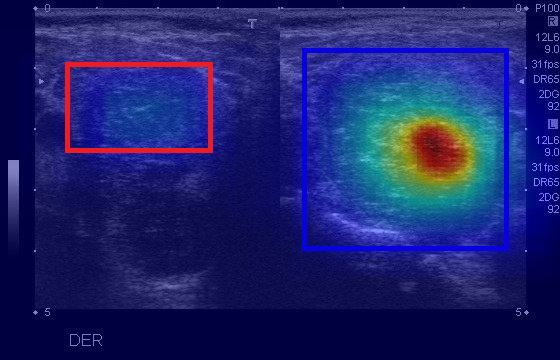

Density map (DM)

DM is commonly used in crowd counting context to estimate objects’ distribution in an image li2020density . We propose DM as a new statistic-based method in the context of XAI by extracting the frequency value of each pixel from boxes predicted by the model in region proposal generation, as shown in Fig. 4. The pixel’s frequency value is calculated by the number of boxes containing that pixel. For an input image , the model detected boxes after the first stage. For any box , let be the set of coordinates . Thus, DM’s output of is the matrix defined as , where is computed:

The more focused boxes a pixel has, the redder colors are indicated in the DM’s explanation. In Fig. 4a, the model detects two boxes containing nodules where the blue box is correct with the ground-truth label, while the red box is false. The DM’s saliency map can explain the blue box with redder colors, indicating that the model focuses on this region to detect the nodule.